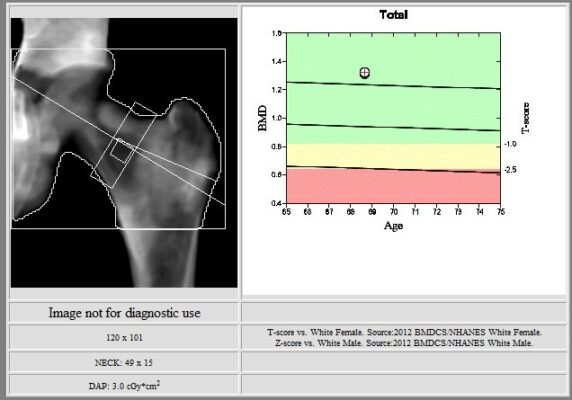

This image shows DXA of the left hip. The left total hip bone mineral density is 1.316 grams per square centimeter, with elevated T-score of 3.1. There are diffuse heterogeneous sclerotic changes.

This table summarizes the results of DXA of the left hip.

The Hologic lumbar spine and left total hip DXA scans demonstrated elevated T scores in a patient with metastatic prostate cancer due to diffuse heterogeneous sclerotic changes. In the setting of skeletal metastatic disease, bone mineral density (BMD) measurements can be artificially increased, leading to inaccurately elevated T-scores. When unusually high BMD values are observed on DXA, results should be interpreted with caution and potential contributions from artifacts, generalized skeletal pathology and focal lesions should be considered.